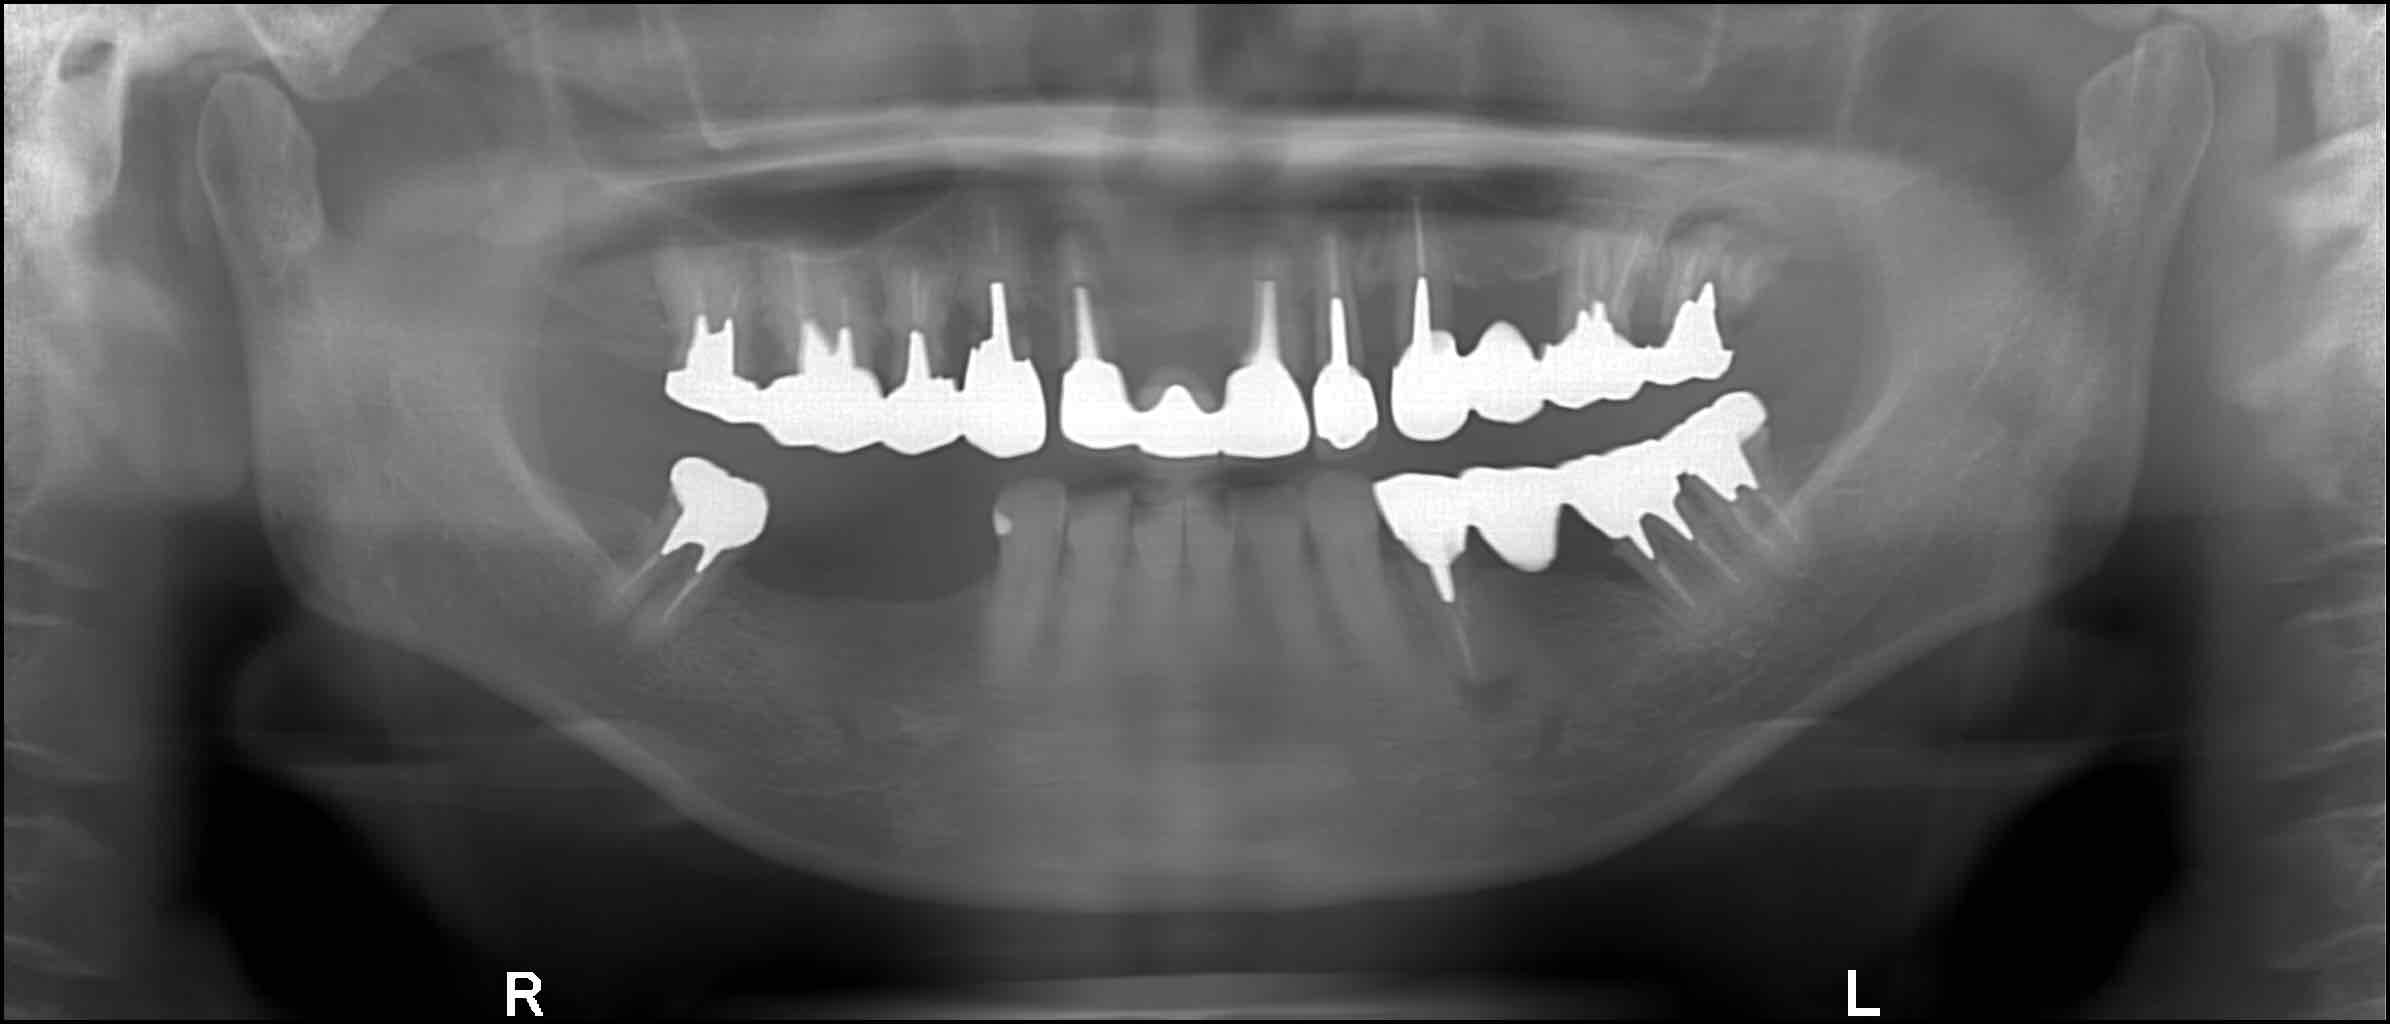

| インプラント | 40歳代 女性 |

|---|---|

| 主訴 |

上下顎の歯が少なくなって、残っている歯も全てぐらぐらして食事が出来ない。 |

| 治療内容 |

インプラント埋入(下顎4本、上顎6本) 【下顎】 【上顎】 |

| 治療結果 |

メンテナンスに継続して来院頂き、⼿術後15年以上経過していますが、インプラントの状態は良好です。 |

| 治療期間 | 5ヶ月 |

| 治療費用 | 下顎 250万円(税込) 上顎 300万円(税込) |

| リスク | 術後の痛み、腫れ。 |

術後レントゲン

術後15年以上が経過していますが、インプラントの状態は良好です。